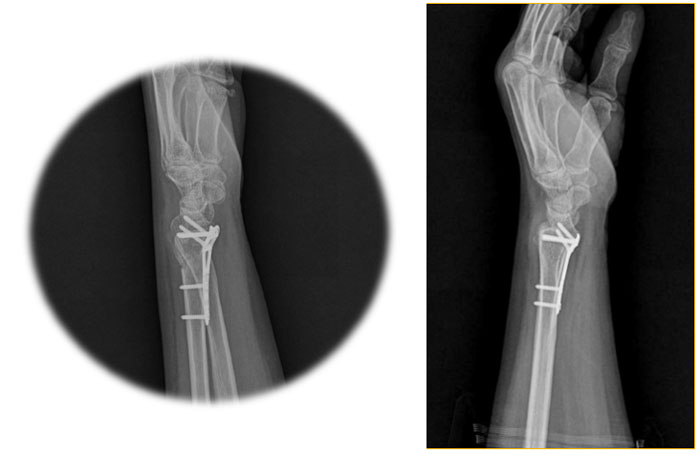

NewColle was developed by collecting feedback from doctors and patients on existing products. Doctors wanted to design for accurate reconstruction and keep the anatomical shape for the healing period, while patients wanted to minimize discomfort during treatment. Thus, TDM’s R&D introduced products that would be extremely thin, structurally rigid as possible, and that can provide various procedures at the same time.

Distal Radius Plates

All NewColle plates are designed to fit the anatomical contours of the distal radius as much as possible. It has small, medium, and large sizes to fit the various sizes of the bones and has also various lengths to handle irregular fracture locations.

The long plate is also available as an option specification, up to eight holes. By setting the plate thickness to 1.5 mm, irritation of soft tissue was minimized.

The screw insertion angle can be up to 15 degrees from the center to both sides, so the fixed angle range is 30 degrees. TDM’s goal is to become one of the leading global medical device manufacturers, and it is ceaselessly moving toward achieving this goal.